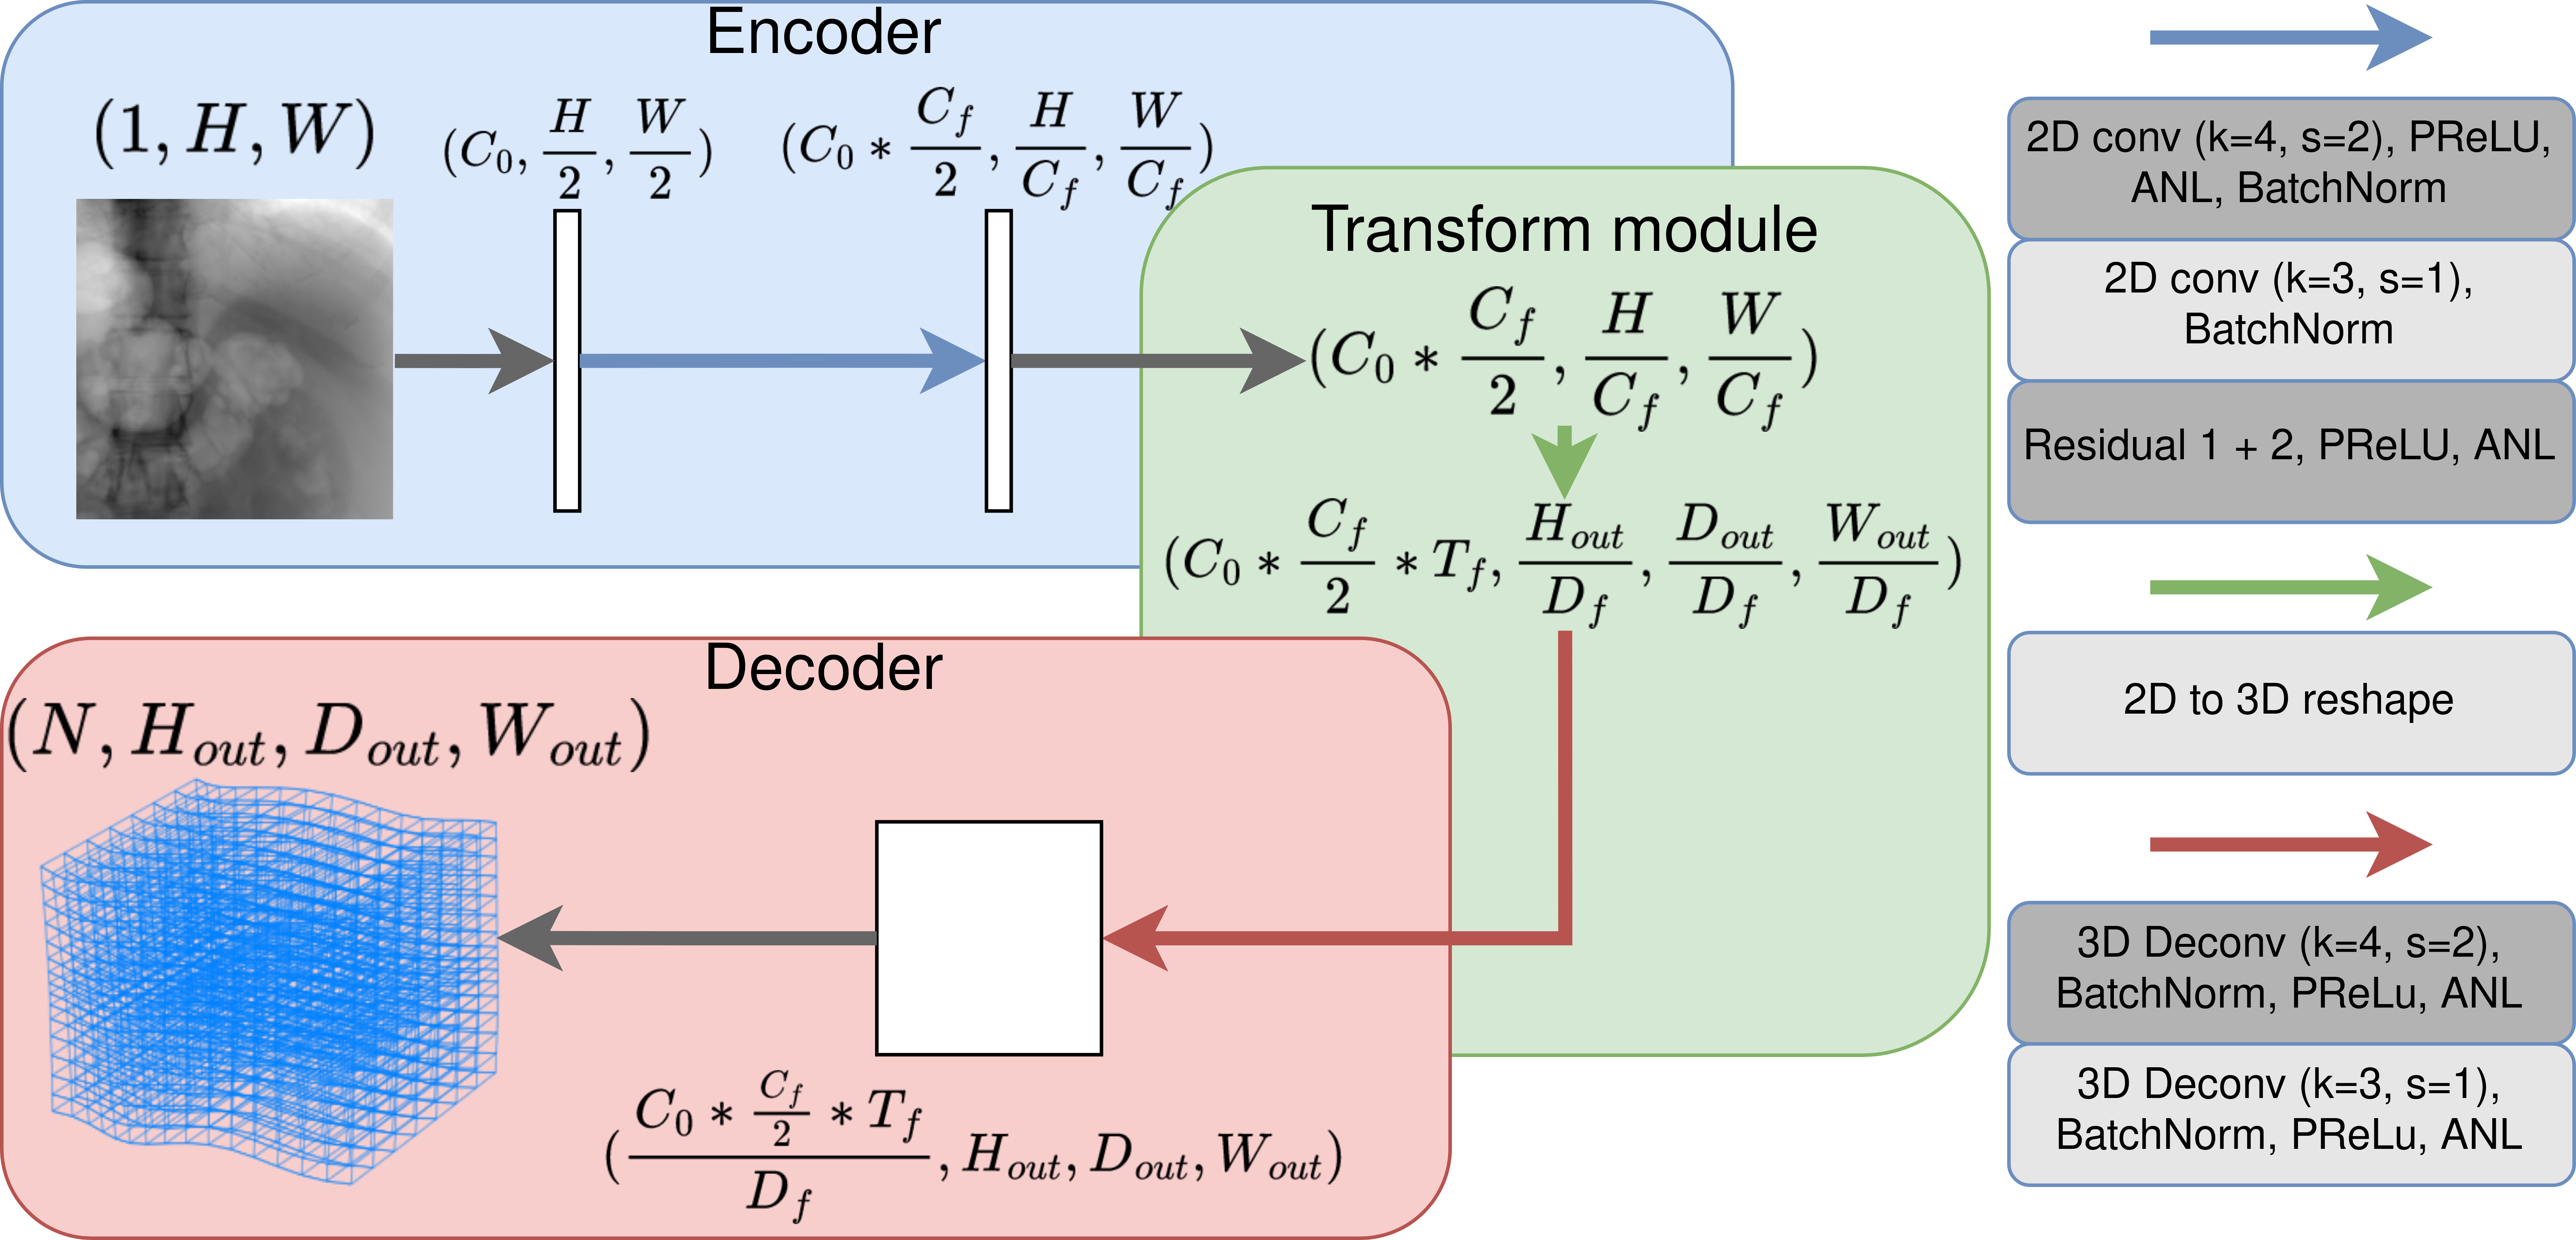

Our network architecture is inspired by the work of Shen et al. shen_patient-specific_2019 which goal is to reconstruct a CT volume from a fluoroscopic image. In this fully convolutional architecture, the direct translation from a dense 2D input to a dense 3D output is a key characteristic to learn fluoroscopy-to-CT mapping.

In order to use this network for 2D-3D registration, the output of the network is now a 3D displacement field representing the total non-rigid + rigid transform of the preoperative CT to the intra-operative anatomy visible in the fluoroscopic image.

This allows the network to predict both global and local displacements in the preoperative CT from the intra-operative fluoroscopic image. We also added several Adversarial Noise Layers (ANL) you_adversarial_2019 to regularize the latent space. The architecture of our network is summarized in figure 2.

The 2D input is an image of size . The output 3D displacement field can also be considered as 3-channel volumetric image, of size . The first convolutional layer, represented by a gray arrow, with and , transforms the input into a feature map with features. For every following Residual Block, H and W are divided by 2 and is multiplied by 2. The last convolutional layer, in gray, with and , is not in a residual block and is followed by a BatchNorm, PRelu and ANL. The transform module performs a 2D to 3D reshape of the feature maps extracted by the encoder and passes them to the decoder. In the decoder, H, D and W are upscaled by a factor of 2 while the number of features is divided by 2 for every two of the layers. An additional deconvolutional layer, in gray, with and , transforms the output features into 2 channels. The 2 channels correspond to the two directions of displacement visible in the projection image. Predicting the displacement component perpendicular to the image plane is very challenging as a deformation in this direction leads to nearly no change in the fluoroscopic image. The network is supervised against the known 3D displacement field using an MSE loss, using AdamW loshchilov_decoupled_2018 () as the optimizer. An ablation study (see table 1) was performed to determine the best values for the hyperparameters .